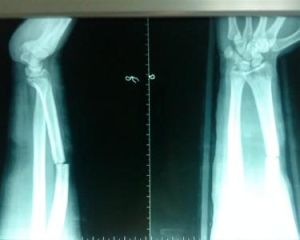

無相關實驗室檢查。X線檢查,前臂正側位X線片,含下尺橈關節,可確診。

外傷史,局部疼痛,腫脹和壓痛,移位明顯者可出現短縮,成角畸形,X線檢查,可確診。